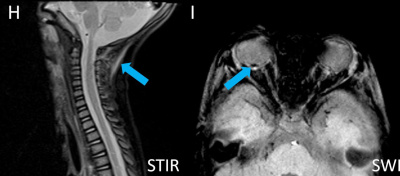

- D) Posteriyor fossada subdural hemoraji

- E) Subdural hematohigroma ile uyumlu yoğun içerikli bileşenler

- F) Verteks düzeyinde lolipop/iribaş (tadpole) işareti

- G) Verteks düzeyinde köprü ven trombozuna/yaralanmasına ait duyarlılık artefaktı

- H) Nukal bağda yaralanma lehine T2 sinyal artışı

- I) Sağ bulbus okulide retinal hemoraji

- Köprü ven trombozu: Manyetik duyarlılık görüntülemede, kortikal ven trasesinde duyarlılık artefaktı olarak ya da “lolipop” ve “iribaş” (tadpole) işareti şeklinde görülür. Vakaların yaklaşık %30-45’inde saptanır.

- Spinal yaralanmalar : Sanılandan daha yaygındır ve olguların yaklaşık %30-40’ında görülür. Genellikle gözden kaçar. En sık saptanan bulgular servikal spinal bağ yaralanmaları ve spinal subdural hematomdur.

- Retinal hemorajiler vakaların yaklaşık %85’inde görülür. Bilateral çok sayıda kanama olması istismar ilişkili yaralanma açısından kuvvetli şüphe oluşturmalıdır. Tanı temelde muayene bulguları ile konulur; ancak manyetik duyarlılığa dayalı görüntüleme (SWI) ve difüzyon görüntüleme de yararlı olabilir.